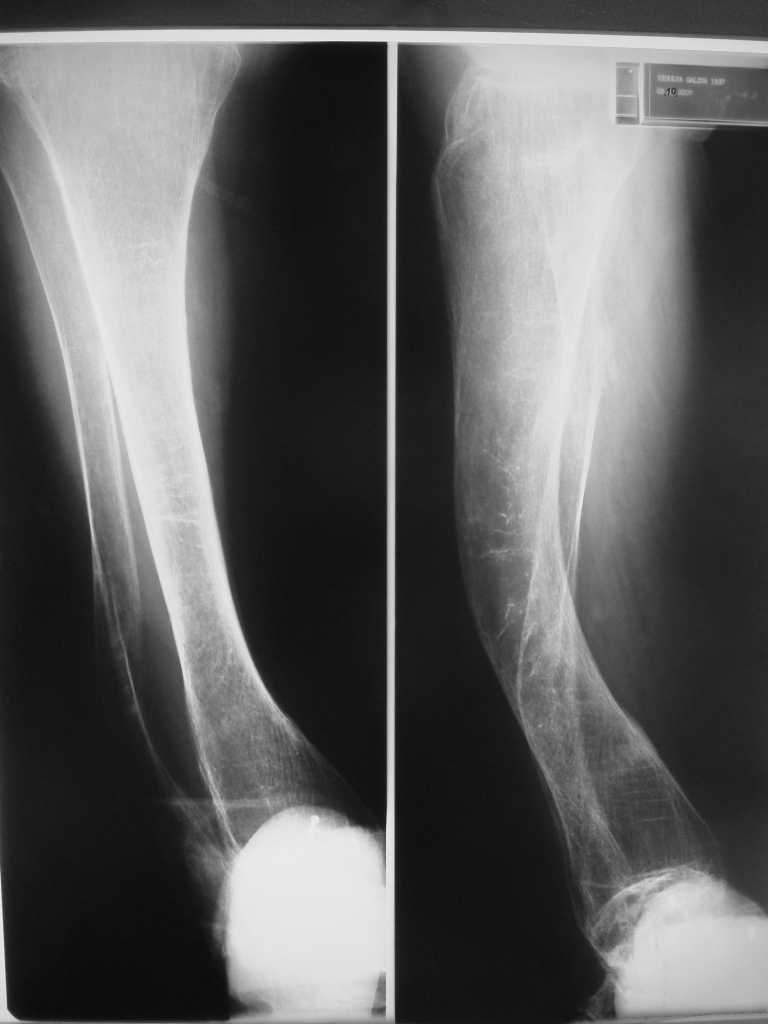

Но даже при малоинвазивной методике лечения применимой для даной больной существуют следующие проблемы: выраженный остеопороз, тонкий кортикал, очень широкий канал.

Контрольные рентгенограммы прилагаю.

Проблема в том, что в сагитальной плоскости угол голеней =30 градусам. Ширина канала 30.